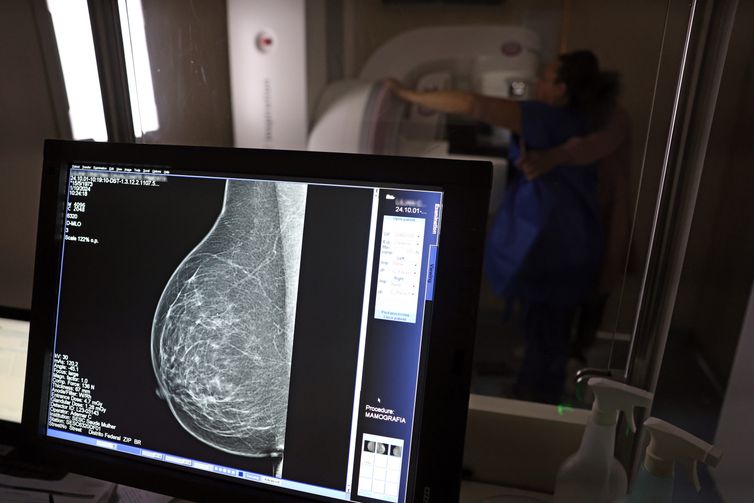

No Outubro Rosa, o Instituto Nacional de Câncer (Inca) estimou 73.610 novos casos este ano no país. É o câncer que mais mata mulheres no Brasil. As mulheres em tratamento pela doença têm o direito de receber o auxílio-doença ou o benefício de prestação continuada.

A vice-presidente da Comissão de Previdência Social Pública da Ordem dos Advogados do Brasil do Rio de Janeiro (OAB-RJ), Danielle Guimarães, destaca que o câncer de mama é uma das doenças que mais afetam mulheres no Brasil, impactando não apenas a saúde física e emocional, mas também a capacidade de trabalho e a segurança financeira das pacientes.